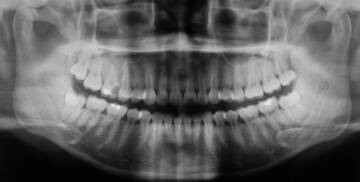

- zdjęcia panoramiczne zębów (całkowite)

Zapewniamy możliwość wykonania zdjęcia panoramicznego zębów (panoramiczne RTG zębów) oraz radiologicznego punktowego (rentgen zębów) wszystkim pacjentom, również nie korzystającym z leczenia w naszej klinice stomatologicznej. W przypadku braku skierowania lekarskiego na badanie istnieje możliwość jego uzyskania po bezpłatnej konsultacji lekarskiej w naszej klinice.

Rentgen zębów to standard w nowoczesnej stomatologii

Dzięki zastosowaniu najnowocześniejszej aparatury radiologicznej firmy Kodak, lidera bezpieczeństwa, zapewniamy najwyższą jakość obrazowania przy najmniejszym z możliwych narażeniu na promieniowanie radiologiczne. Wykwalifikowany i doświadczony personel zadba o państwa bezpieczeństwo i maksymalną korzyść z przeprowadzonego badania radiologicznego.